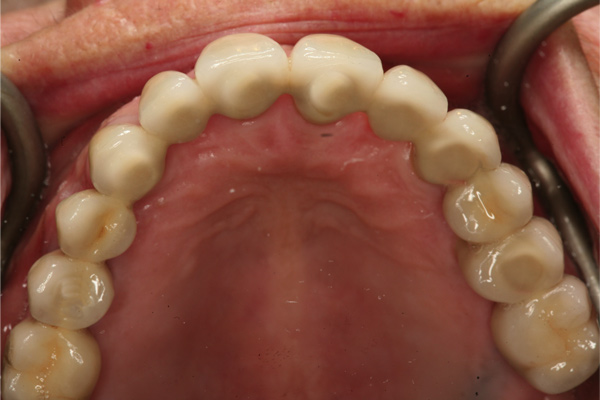

Fig 12. Frontal view (Fig 12) and occlusal view (Fig 13) of clinical application of dual-axis principles. (Images courtesy of Costa Nicolopoulos, BDS)

Figure 12

Fig 13. Frontal view (Fig 12) and occlusal view (Fig 13) of clinical application of dual-axis principles. (Images courtesy of Costa Nicolopoulos, BDS)

Figure 13

With the increased application of this concept, more options have been introduced, including 24-degree and 36-degree correction (Figure 11 through Figure 13). At present, larger angular corrections are available with external hexagon connection systems, while the 12-degree connection is also available in most internal connection configurations.

The author has used the dual-axial implant fixture unconventionally in the anterior mandible in an orientation that avoids perforation into the floor of the mouth (Figure 8).5 Dual-axial implants have also been used to avoid critical anatomic structures, such as the maxillary sinuses (Figure 9) and inferior alveolar nerves (Figure 10),47 thereby reducing the need for grafting procedures. Because these implants have subcrestal angular correction, they can be used with standard uniaxial abutments in a common path of insertion, thus enabling screw retention.